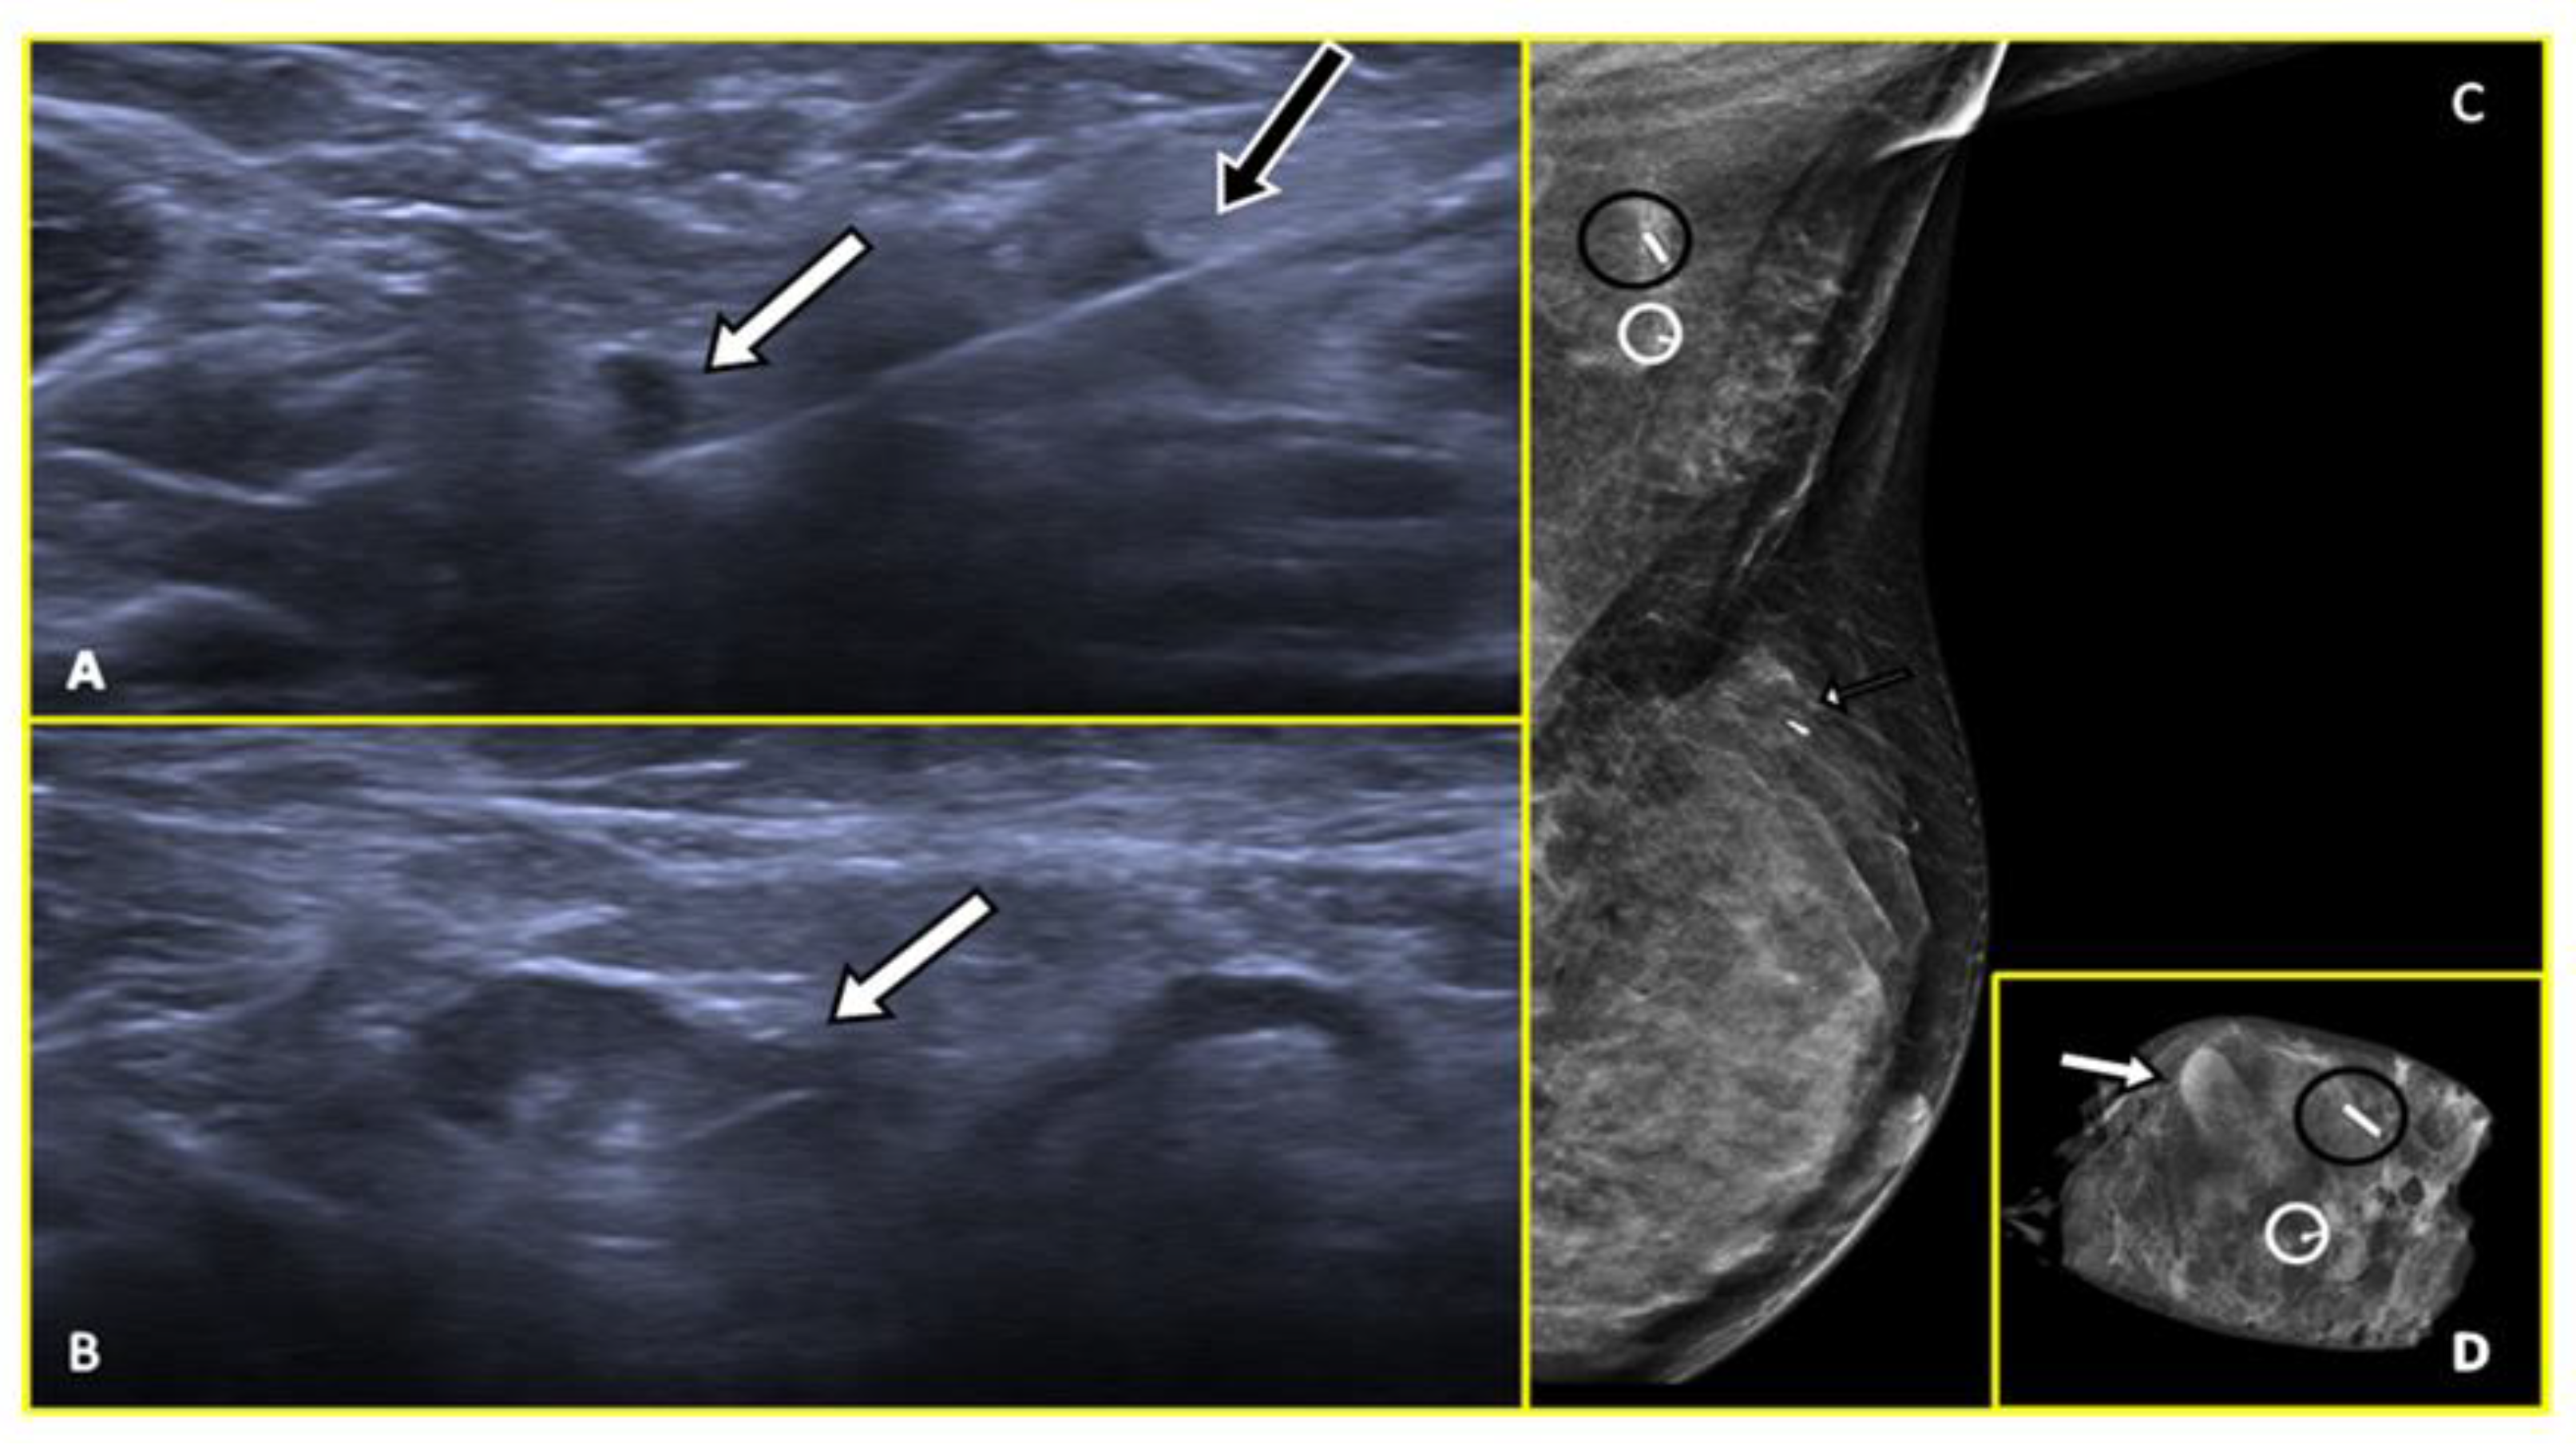

2.2. Carbon Suspension-Based Localization

- Hartmann, S.; Stachs, A.; Kühn, T.; de Boniface, J.; Banys-Paluchowski, M.; Reimer, T. Targeted Removal of Axillary Lymph Nodes After Carbon Marking in Patients with Breast Cancer Treated with Primary Chemotherapy. Geburtshilfe Frauenheilkd. 2021, 81, 1121–1127. [Google Scholar] [CrossRef]

- Hartmann, S.; Kühn, T.; de Boniface, J.; Stachs, A.; Winckelmann, A.; Frisell, J.; Wiklander-Bråkenhielm, I.; Stubert, J.; Gerber, B.; Reimer, T. Carbon Tattooing for Targeted Lymph Node Biopsy after Primary Systemic Therapy in Breast Cancer: Prospective Multicentre TATTOO Trial. Br. J. Surg. 2021, 108, 302–307. [Google Scholar] [CrossRef]

- Choy, N.; Lipson, J.; Porter, C.; Ozawa, M.; Kieryn, A.; Pal, S.; Kao, J.; Trinh, L.; Wheeler, A.; Ikeda, D.; et al. Initial Results with Preoperative Tattooing of Biopsied Axillary Lymph Nodes and Correlation to Sentinel Lymph Nodes in Breast Cancer Patients. Ann. Surg. Oncol. 2015, 22, 377–382. [Google Scholar] [CrossRef]

- Natsiopoulos, I.; Intzes, S.; Liappis, T.; Zarampoukas, K.; Zarampoukas, T.; Zacharopoulou, V.; Papazisis, K. Axillary Lymph Node Tattooing and Targeted Axillary Dissection in Breast Cancer Patients Who Presented as CN+ Before Neoadjuvant Chemotherapy and Became CN0 After Treatment. Clin. Breast Cancer 2019, 19, 208–215. [Google Scholar] [CrossRef]